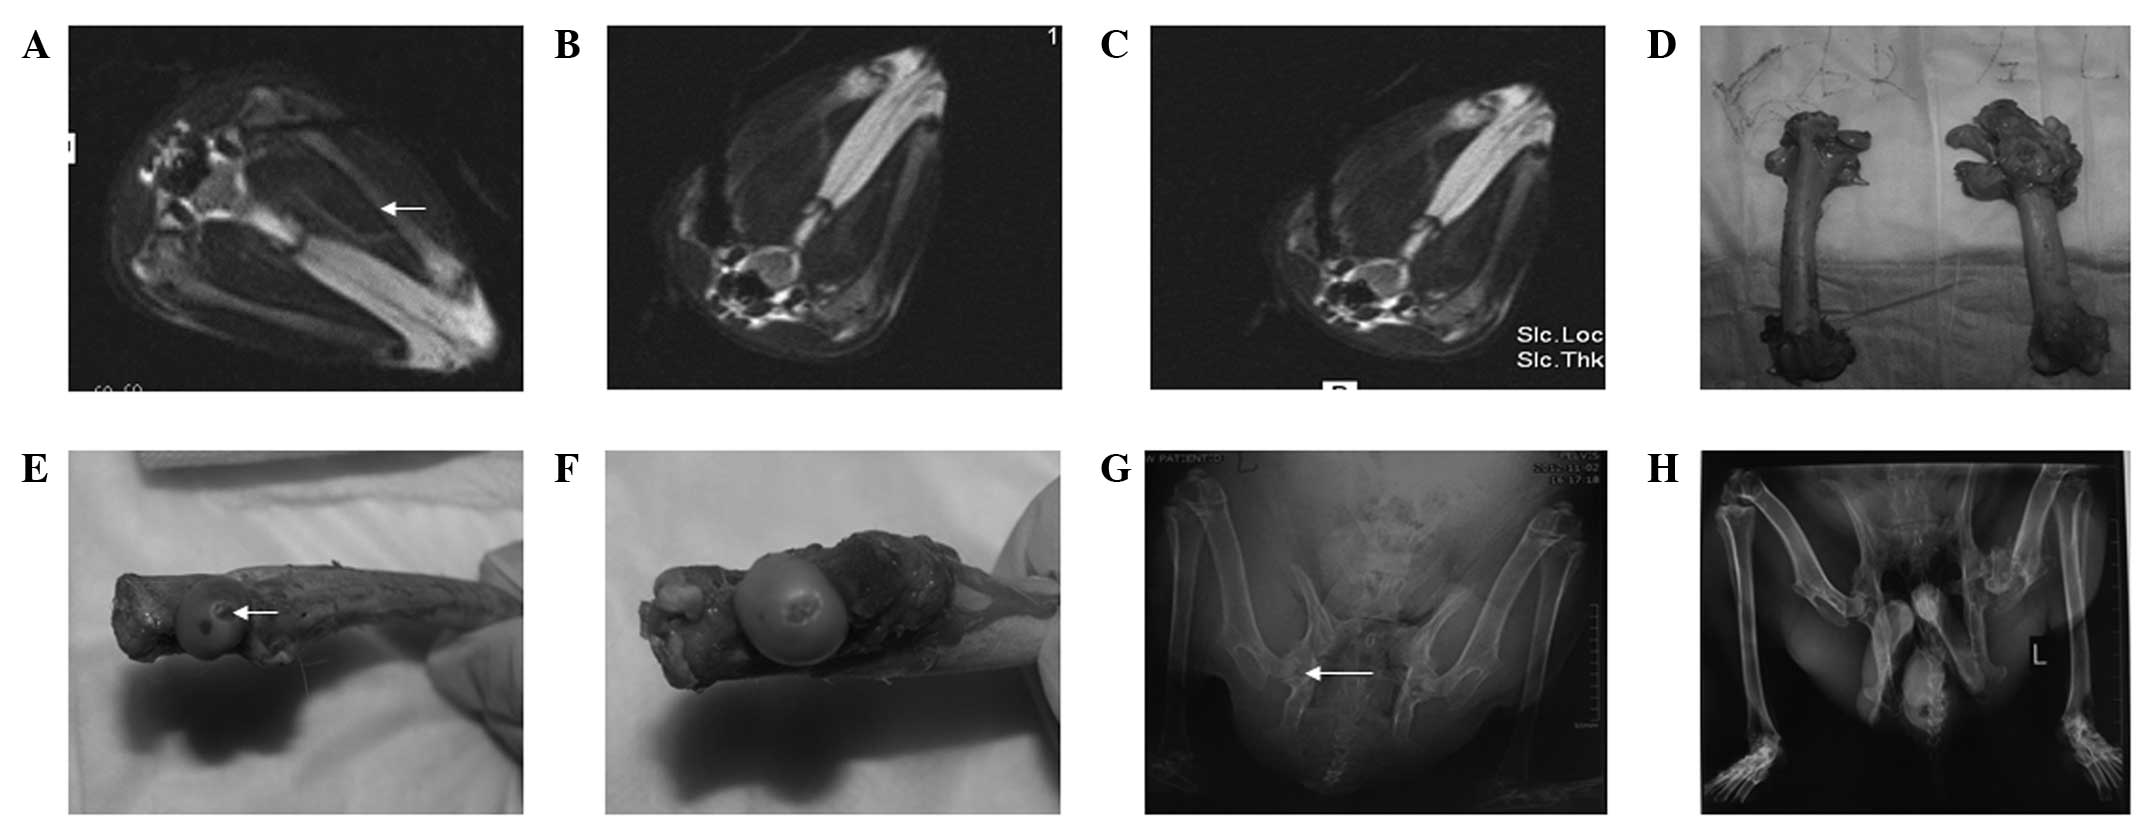

Figure 1

Surgery of the rabbits (groups I and II) was performed in an open 0.23-T MRI system. (A) As guided by MRI, the guide pin was inserted into the bones and located at a position 5 mm below the articular cartilage. (B) In group I rabbits, an ice ball appeared following two freeze-thaw cycles. (C) In group II, one freeze-thaw cycle was performed. (D) At week 4 following the establishment of the model, the femoral head contour was smooth and the cartilage surface was intact, without any defects detected (left, group I left femoral head; right, group II right femoral head). At week 12 following surgery the (E) left femoral head cartilage was defected, as indicated with the arrow, and (F) the right femoral head cartilage was almost integral. (G) At week 8 following surgery, X-ray images showed that the left femoral head had cystic lesions, as indicated with the arrow, while the right femoral head had no abnormal changes. (H) At week 12 following surgery, X-ray images showed that the left femoral head had collapsed, but the right femoral head remained intact. MRI, magnetic resonance imaging.

To establish a novel ONFH animal model using an MRI-guided argon-helium cryotherapy system, 48 rabbits were used. In group I, the left femoral head of every rabbit received two cycles of argon-helium freezing-thawing (Fig. 1B), while in group II, the right femoral head of each rabbit received only one cycle of argon-helium freezing-thawing (Fig. 1C).

In the experiments, none of the rabbits exhibited skin necrosis or infection and there were no mortalities. The femoral head contours of the rabbits in the two groups were smooth and the cartilage surfaces were integral, without any defects detected at week 4 following surgery (Fig. 1D). The femoral head contours of the rabbits in group I became pale, flat and mushroom-shaped, with some bones collapsing at week 12 following surgery (Fig. 1E). Three months after surgery, the right femoral head cartilage was almost intact (Fig. 1F). These results indicated that a novel ONFH animal model using an MRI-guided argon-helium cryotherapy system was successfully established.

Radiological analysis

To further determine the differences between groups I and II, radiological analyses were performed. In group I, the bone densities of the femoral heads in 10 rabbits were decreased at week 4 following surgery. Cystic changes appeared at week 8 (Fig. 1G) and seven femoral heads were collapsed at week 12 following surgery (Fig. 1H; Table I). In group II, the bone densities of the femoral heads in nine rabbits were reduced at week 4 following surgery. Cystic changes and narrowed hip joint space were observed at week 8 and two femoral heads were collapsed at week 12 (Table I).